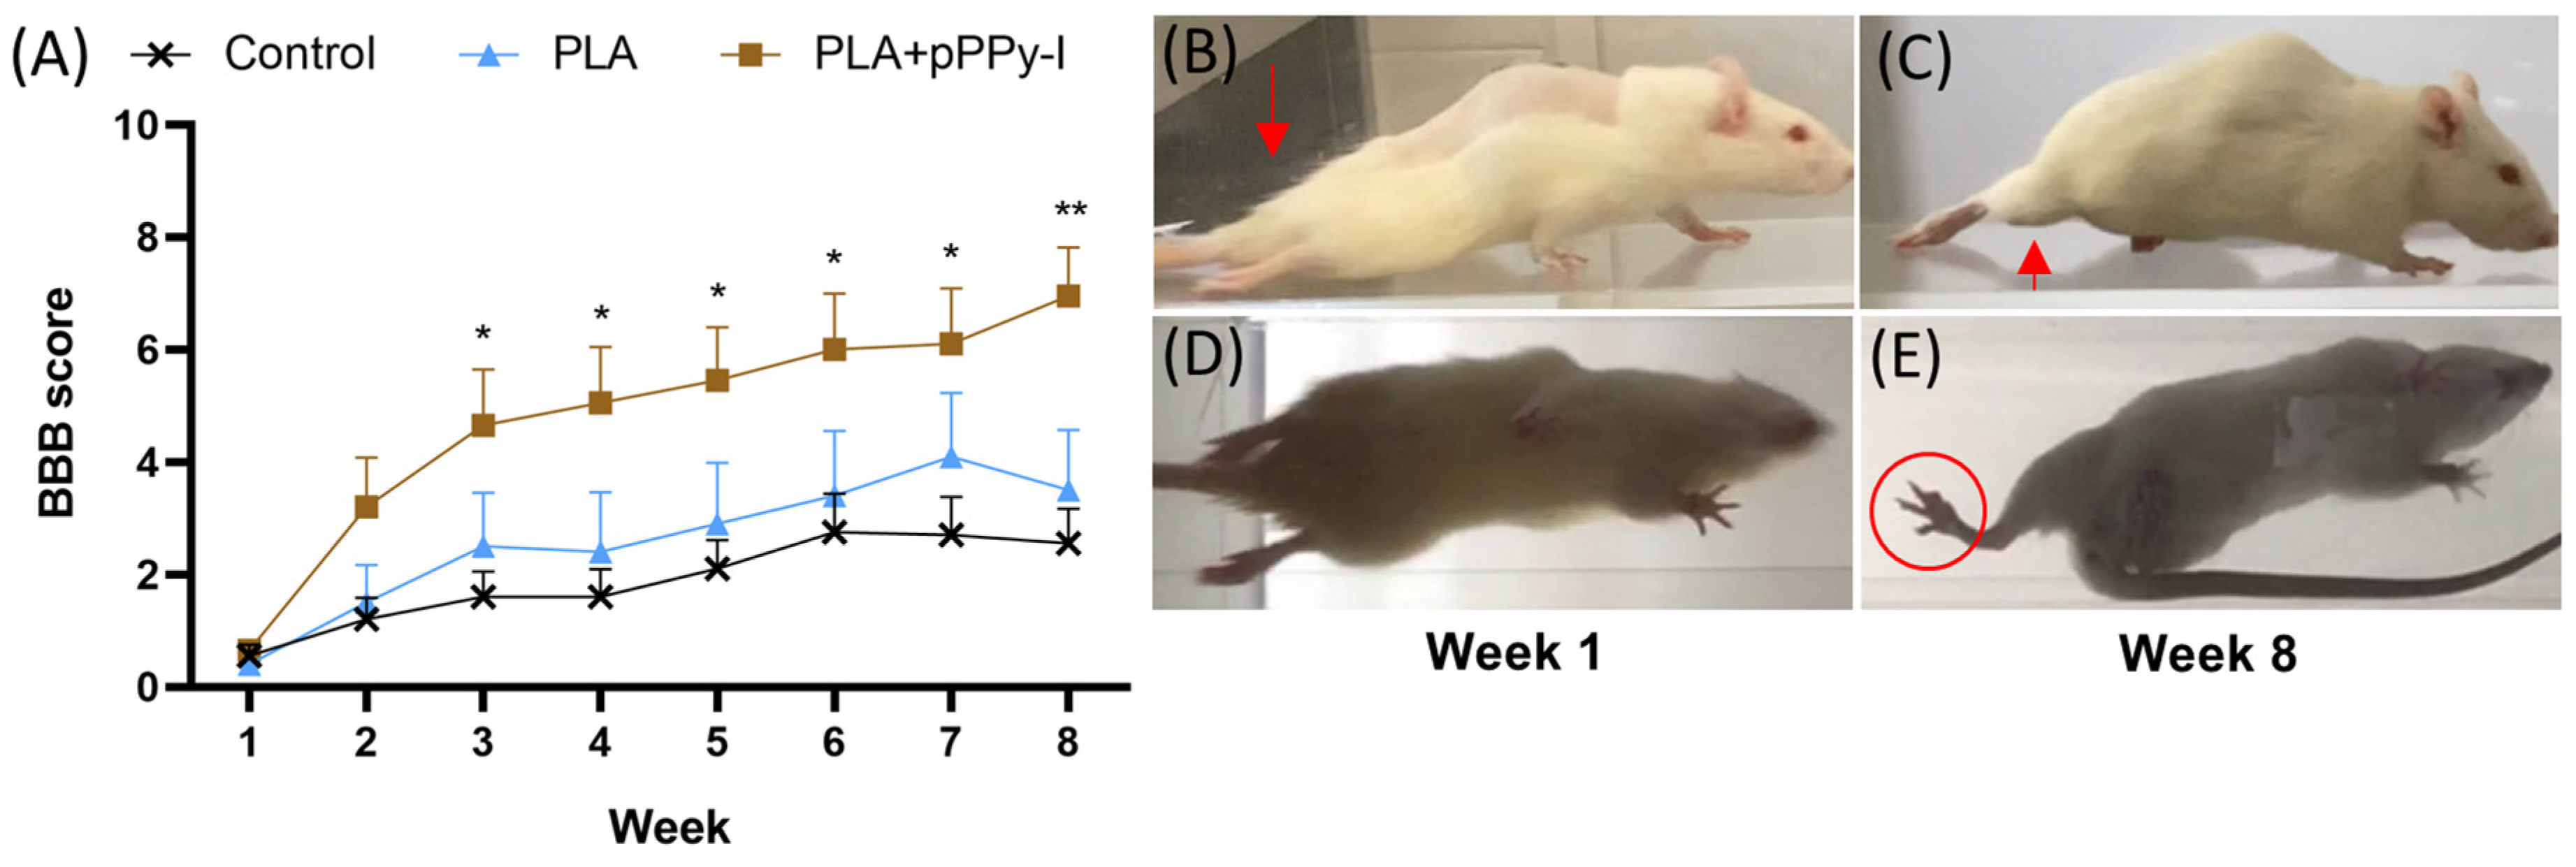

3.2. Implanted Animals Showed Improved Motor Recovery